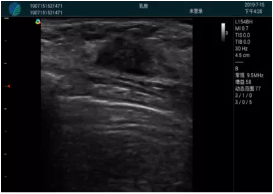

清晰顯示腺體內(nèi)低回聲快影,邊界清晰,包膜較光滑

確定進(jìn)針路徑并實(shí)時(shí)監(jiān)測(cè)抽吸針與腫塊位置關(guān)系

抽吸針進(jìn)入腫塊內(nèi)部進(jìn)行旋切

抽吸過程中可見腫塊明顯縮小,并根據(jù)腫塊位置改變針道位置

抽吸旋切后再進(jìn)行超聲復(fù)查,原腫塊區(qū)域未見殘留組織及出血